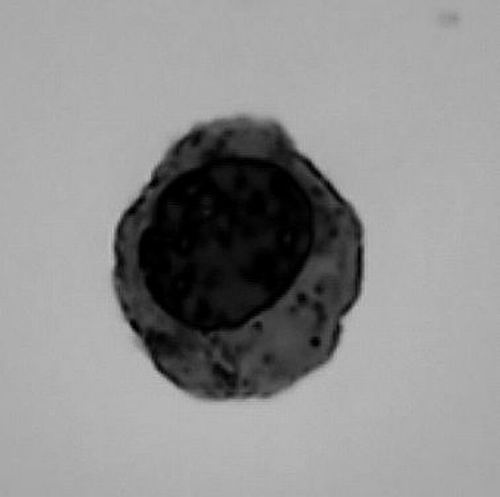

③光鏡下觀察到的人類(lèi)紅細(xì)胞終末發(fā)育的晚期。受訪(fǎng)者供圖

紅細(xì)胞發(fā)育過(guò)程可以分為多個(gè)階段。成熟的紅細(xì)胞通常是雙凹圓盤(pán)形且沒(méi)有細(xì)胞核,因此,在其發(fā)育過(guò)程中,前體細(xì)胞需要經(jīng)歷染色質(zhì)壓縮、細(xì)胞核極化等過(guò)程,哺乳動(dòng)物的紅細(xì)胞最終還要經(jīng)歷“脫去細(xì)胞核”的關(guān)鍵步驟,以產(chǎn)生沒(méi)有細(xì)胞核的紅細(xì)胞。

李湘盈介紹,科學(xué)家早就觀察到紅細(xì)胞在成熟過(guò)程中體積變小,伴隨其染色質(zhì)逐漸壓縮,核容量最終減少到原來(lái)的1/3。而整個(gè)過(guò)程中仍然需要保持血紅蛋白基因等紅細(xì)胞功能相關(guān)基因的表達(dá)。“紅細(xì)胞發(fā)育中的染色質(zhì)壓縮過(guò)程是否有一定的程序性規(guī)律與機(jī)制,以及染色質(zhì)高度壓縮狀態(tài)下如何維持基因表達(dá),一直是懸而未決的問(wèn)題?!崩钕嬗f(shuō)。